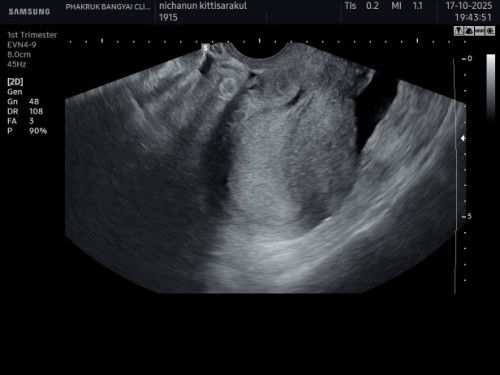

วันนี้ฝากครรภ์ที่โรงพยาบาล อัลตร้าซาวน์ทางหน้าท้อง ช่องคลอด เจอแต่ถุงตั้งครรภ์ แม่ๆมีประสบการณ์นี้มั้ยคะ ว่ามาเจอตัวน้องตอนไหน

ไปฝากท้องเจอแต่ถุงตั้งครรภ์